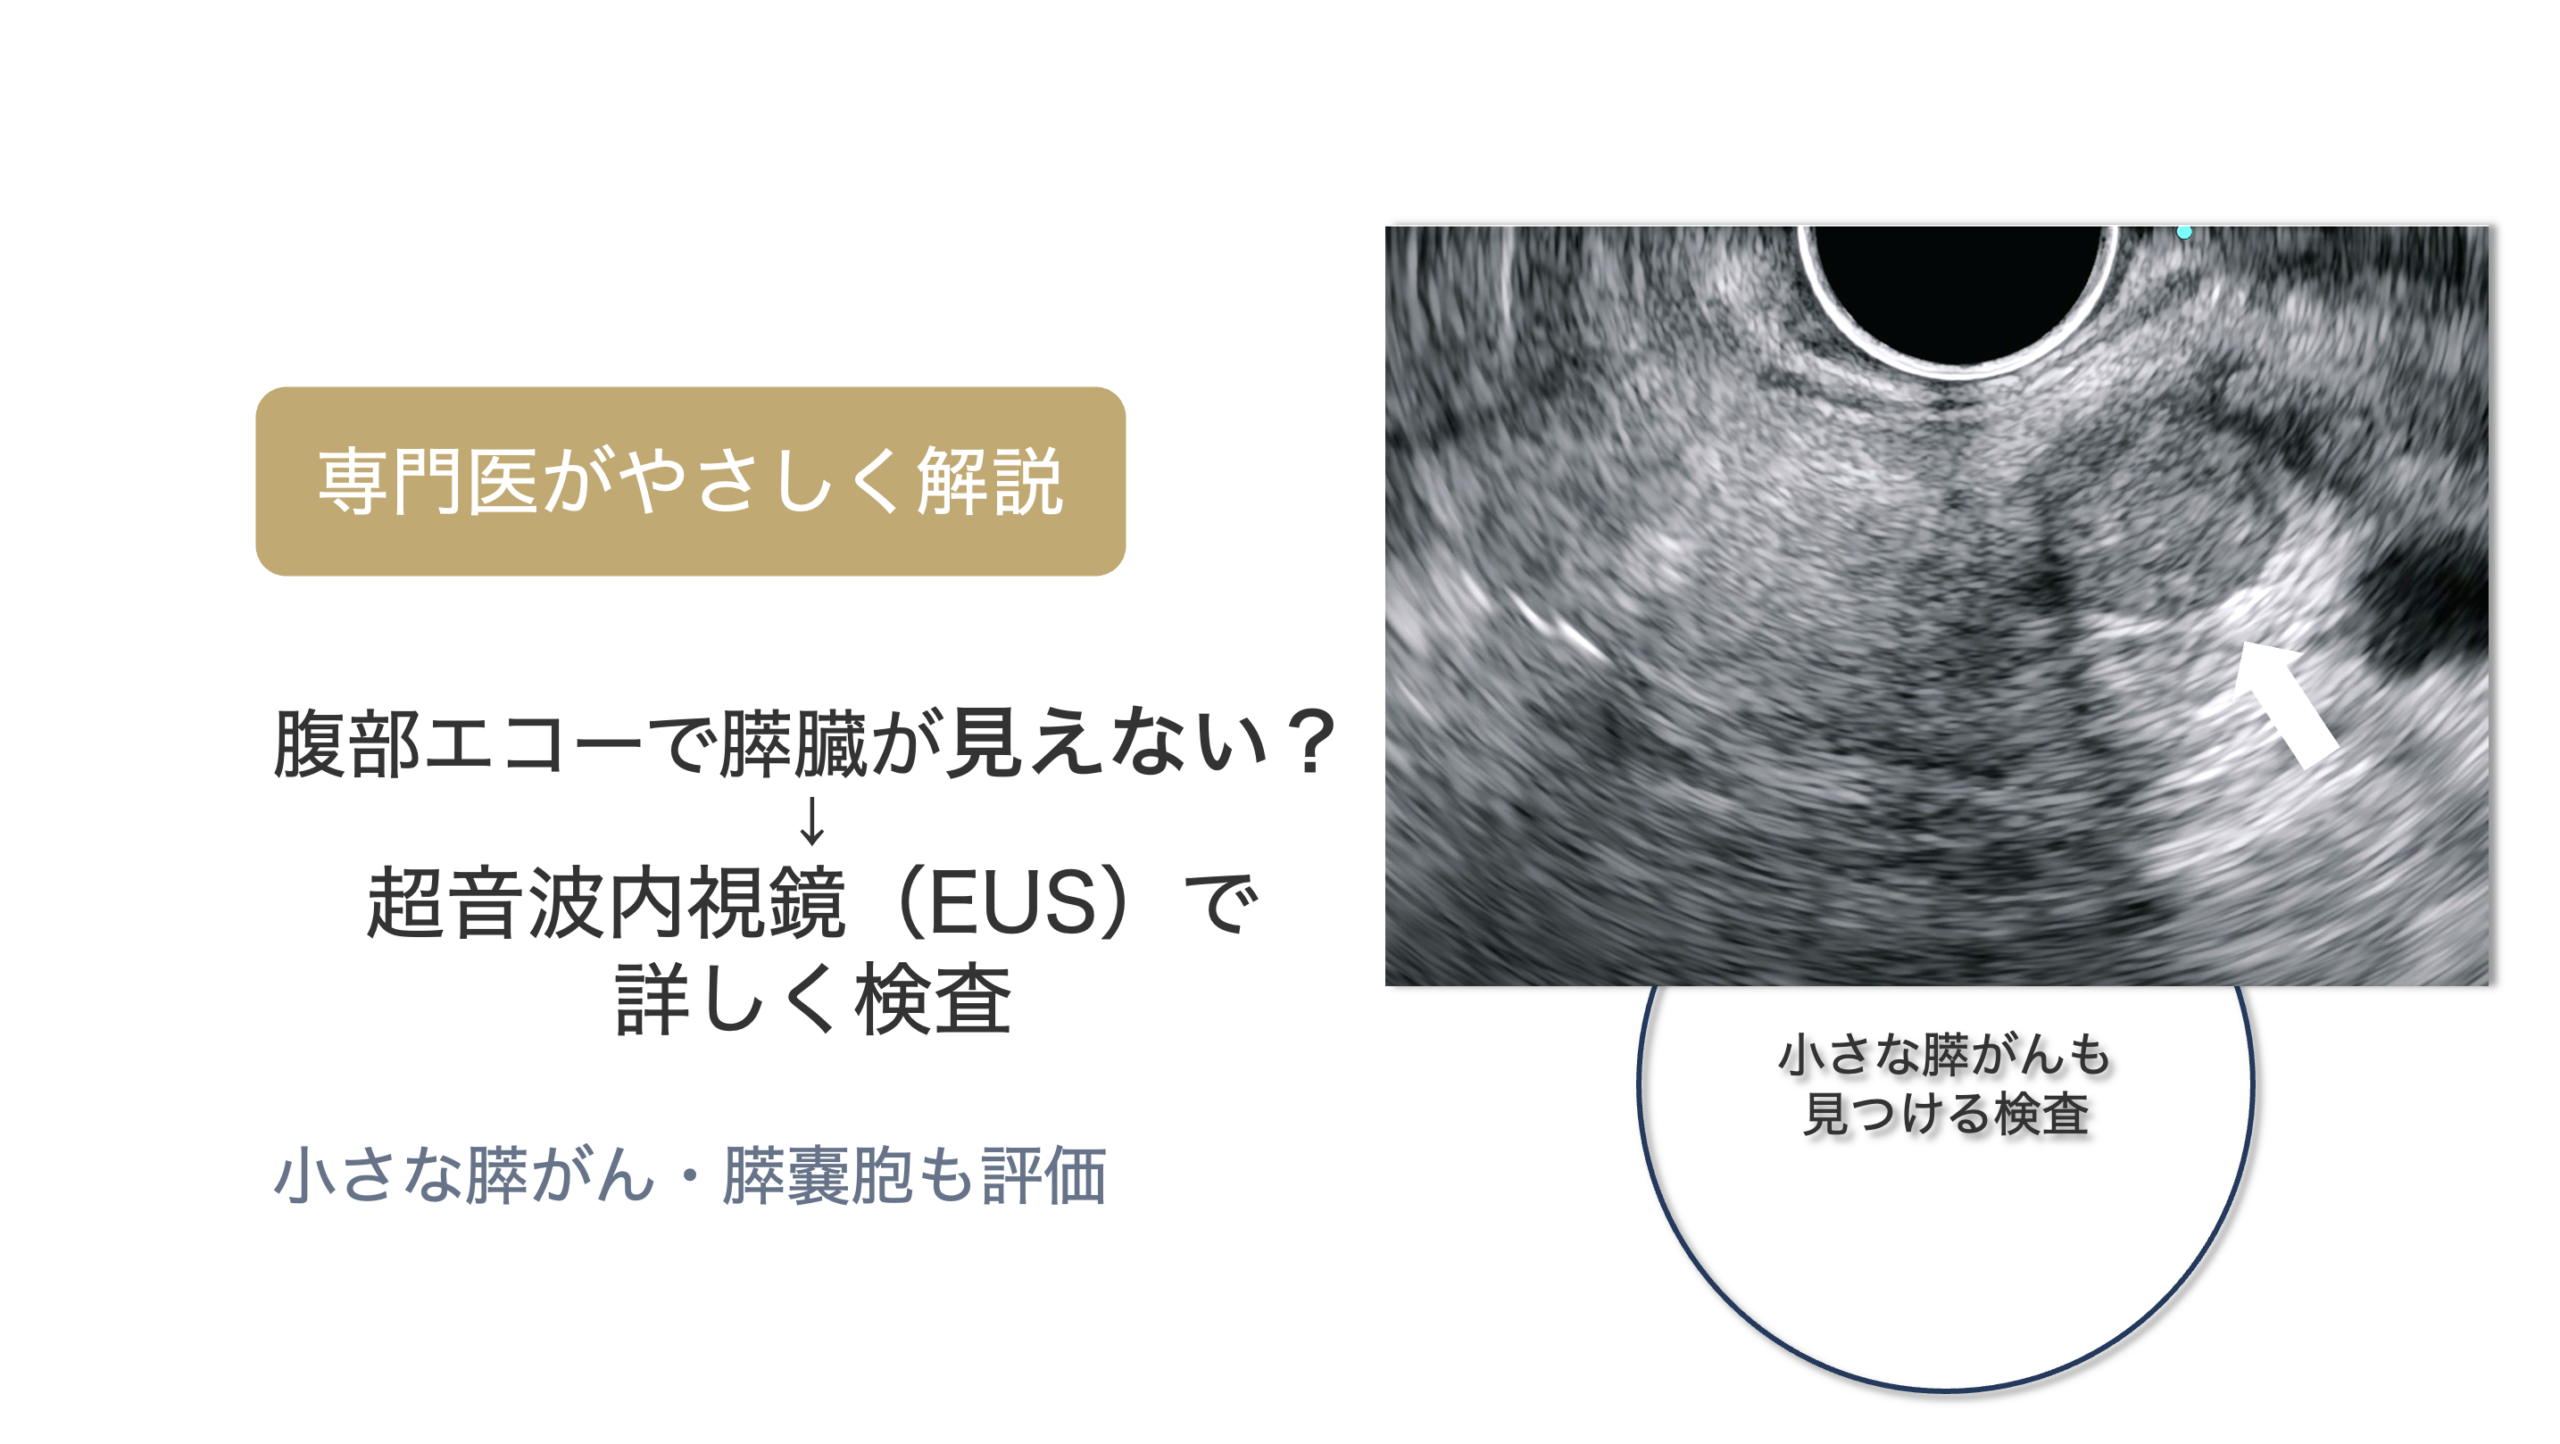

ただし、嚢胞の中に結節があるかどうか、主膵管の変化があるか、小さな病変が隠れていないかなど、通常の画像検査だけでは判断が難しいことがあります。

そのような場合に役立つのが、超音波内視鏡(EUS)です。

超音波内視鏡(EUS)は、内視鏡の先端についた超音波装置で、胃や十二指腸の内側から膵臓をすぐ近くで観察する検査です。

お腹の上から行う腹部エコーでは見えにくい膵臓も、EUSではより詳しく観察できるため、IPMNの評価や小さな膵がんの発見に役立つことがあります。

特に、IPMNの経過観察中に「もう少し詳しく調べたい」と判断される場合には、EUSが有用です。

超音波内視鏡(EUS)では、膵嚢胞の内部や壁の状態まで詳しく観察することができます